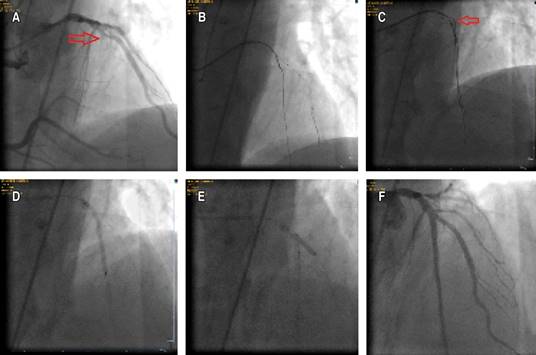

Figure 2: A) The red arrow shows the ambiguous proximal cap. B) The microcatheter could not be advanced despite the support of an anchor balloon. C) The red arrow shows the knuckled hydrophilic wire going down in the subintimal area around the calcium. D) Implantation of a 3 × 38 mm DES in the left anterior descending artery. E) Implantation of a 2.75 × 20 mm DES in the diagonal branch via TAP technique. F) Final appearance.

The second case was a 55-year-old male with a history of cerebrovascular disease. He was also referred to our CTO tertiary center for retry PCI of LAD CTO lesion with heavy calcification and a J-CTO score of 3 (Figure 2A). MRI revealed viability in the anterior wall and a large diagonal at the proximal cap. Again, all the steps mentioned above failed to advance the microcatheter over the wire, which could be advanced to the distal part of the vessel through the true lumen (Figure 2B). A hydrophilic wire was again knuckled and advanced around the CTO body in the subintimal space (Figure 2C). A 2 × 12 mm balloon was advanced over this wire and inflated at 6 atm. After cracking the external calcium, the microcatheter could be advanced over the wire in the true lumen. A 3 × 38 mm Drug-Eluting Stent (DES) was implanted in the LAD (Figure 2D). Then, a 2.75 × 20 mm DES was implanted in the diagonal branch using the TAP technique, and the procedure was finished successfully (Figure 2E-F).